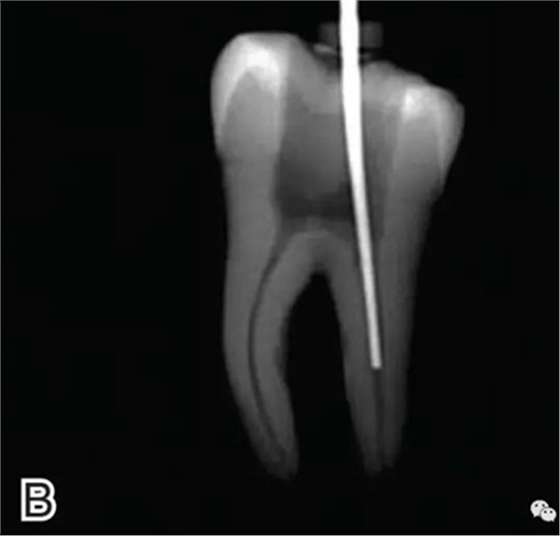

2、選擇垂直加壓器

選擇的小號(hào)垂直加壓器應(yīng)能自由到達(dá)距根尖4~5 mm(有學(xué)者提出3~4 mm)的位置并能輕微接觸根管壁;中號(hào)垂直加壓器應(yīng)能自由到達(dá)距根尖7~8 mm的位置并能輕微接觸根管壁;大號(hào)垂直加壓器應(yīng)能自由到達(dá)距根尖10~11 mm的位置并能輕微接觸根管壁。用橡皮片做好標(biāo)記(圖2)。

圖2 選擇垂直加壓器,A.試垂直加壓器 B.垂直加壓器在根內(nèi)的位置